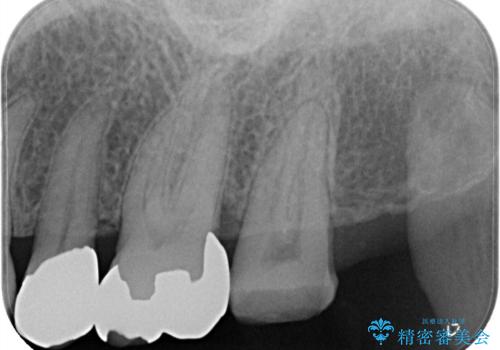

- 歯のかぶせ物が外れてしまったとのことでご来院された患者様です。左上の奥歯のかぶせ物が外れてしまった後、長期間経過したために、歯が動いて下の歯と手前の歯にぶつかってしまっていました。そのため、まずはレントゲンで内部の神経の位置を慎重に把握しながら、仮歯で歯の位置を調整させていただきました。その後、型どりを行い精密なセラミッククラウンにて治療いたしました。術後の経過は良好です。

今回、歯の位置を調整するのに、矯正治療で利用されるセパレーションゴムにて手前の歯との間を離開しています。これを行わないと、内部の神経が露出するリスクがあります。